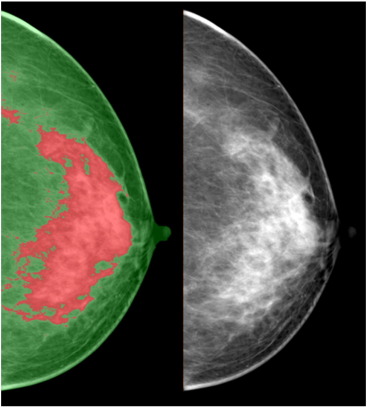

Segmentasi dilakukan untuk memisahkan area yang berisi kanker dari latar belakang dan jaringan payudara normal. Ini melibatkan teknik pemrosesan citra yang mampu untuk mengidentifikasi dan mengisolasi area kanker.

Setelah area kanker tersegmentasi, langkah selanjutnya adalah menghitung diameter kanker. Ini dapat dilakukan dengan mengukur jarak antara titik-titik ekstrem atau melalui analisis morfologi matematika untuk mengidentifikasi batas diameter.

Contoh perhitungan diameter kanker payudara pada modalitas mammography ditunjukkan pada video berikut ini: